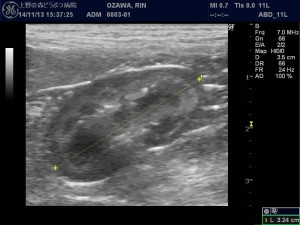

こんにちは 上野の森どうぶつ病院の 諌山です。 スタッフに次々風邪を移したようで、スタッフ全員かぜっぴきの病院…